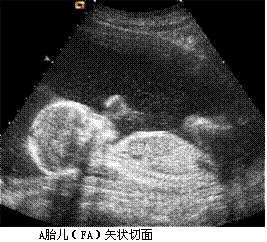

孕妇,30岁,孕2产0孕22周。超声(孕12周):宫内妊娠,单绒毛膜囊双羊膜囊双活胎,A胎儿NT0.32cm,B胎儿NT0.12cm。孕22周复查超声如下图。

孕妇,30岁,孕2产0孕22周。超声(孕12周):宫内妊娠,单绒毛膜囊双羊膜囊双活胎,A胎儿NT0.32cm,B胎儿NT0.12cm。孕22周复查超声如下图。<br /><img s